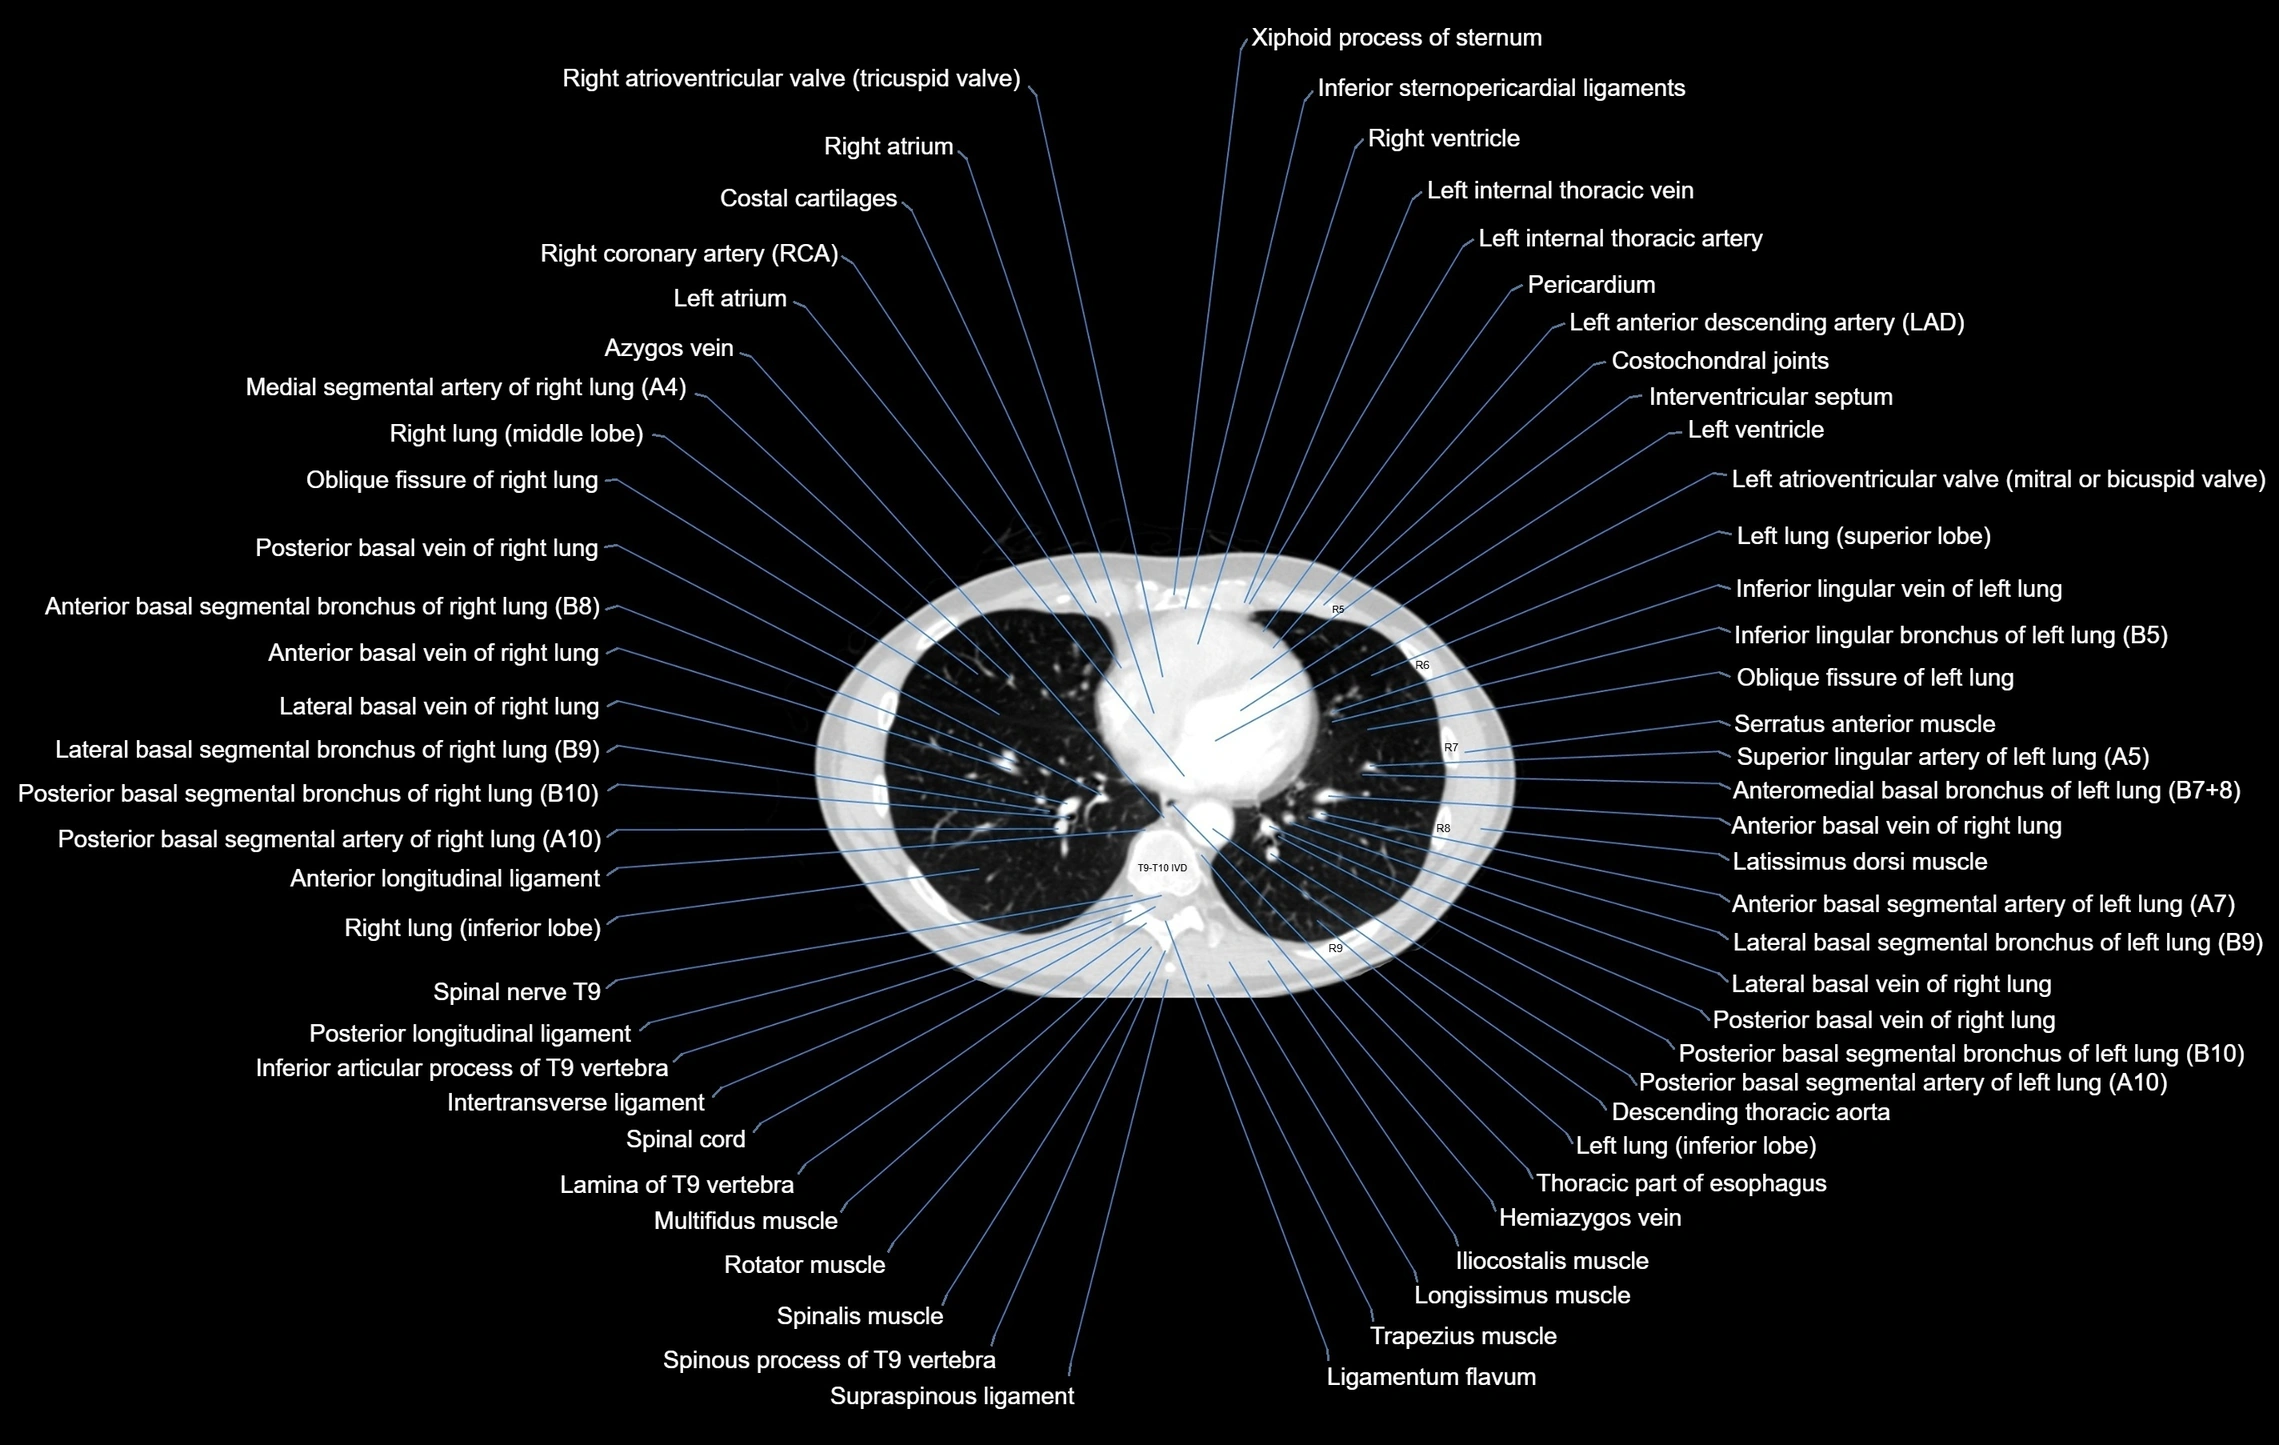

- Anterior basal segmental artery of right lung

- Anterior basal segmental bronchus of right lung (B7+8, B8)

- Anteromedial basal bronchus of left lung (B7+8)

- Descending thoracic aorta

- Hemiazygos vein

- Interventricular Septum

- Lateral basal segmental bronchus of left lung (B9)

- Lateral basal segmental bronchus of right lung (B9)

- Lateral basal vein of right lung

- Left atrioventricular valve (mitral or bicuspid valve)

- Left atrium

- Left ventricle

- Posterior basal segmental artery of left lung

- Posterior basal segmental artery of right lung

- Posterior basal segmental bronchus of left lung (B10)

- Posterior basal segmental bronchus of right lung (B10)

- Posterior basal vein of left lung

- Posterior basal vein of right lung

- Right atrioventricular valve (tricuspid valve)

- Right atrium

- Right coronary artery (RCA)

- Right ventricle

- Thoracic part of esophagus